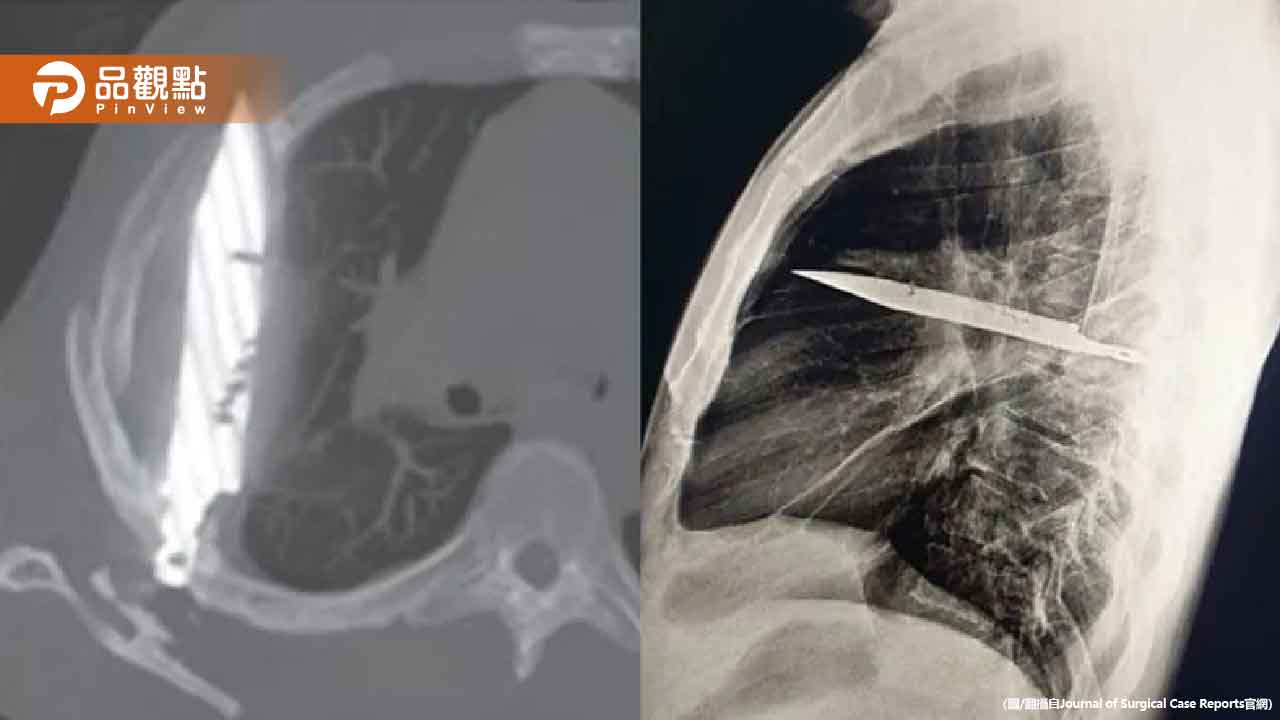

經過詳細問診,患者回憶起8年前曾捲入一場暴力衝突,當時他的臉部、背部、胸部及腹部都遭到刀械攻擊。雖然當時接受了醫療處置,但沒想到竟有一把刀片遺留在體內。為了確認情況,醫院對患者進行了胸部X光檢查,結果令所有人大吃一驚。

X光影像清楚顯示,患者的胸腔內赫然插著一把刀。這把刀從右肩胛骨刺入,神奇地避開了所有重要器官,就這樣在他體內停留了長達8年之久。這也解釋了為何患者多年來一直正常生活,直到最近才出現異常症狀。